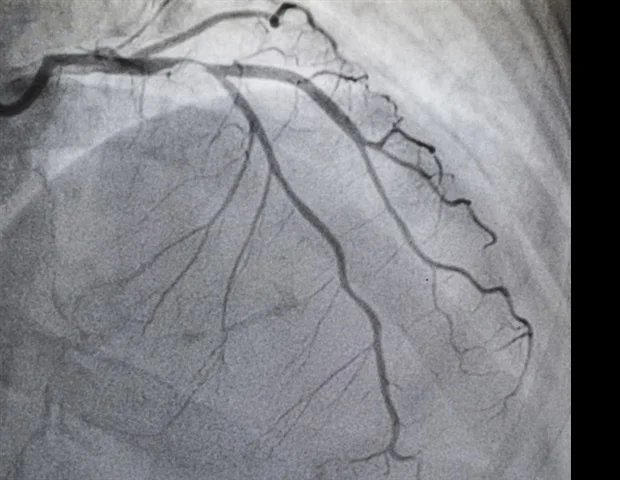

Le TAVR est une procédure mini-invasive dans laquelle les médecins insèrent une nouvelle valvule cardiaque à travers un vaisseau sanguin sans ouvrir la poitrine, tandis que le SAVR nécessite une intervention chirurgicale à cœur ouvert pour ouvrir la poitrine afin de retirer l'ancienne valvule et de coudre une valvule de remplacement. Au cours de la dernière décennie, les cliniciens ont fait passer le TAVR d'une option pour les patients à haut risque à un traitement de première intention pour les patients de tous niveaux de risque.